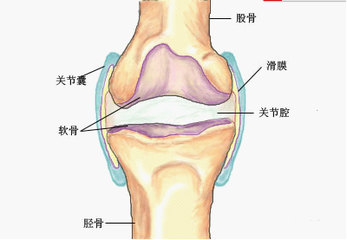

儿童髋关节滑膜炎,也被称为一过性髋关节滑膜炎或暂时性髋关节滑膜炎,是儿童髋关节部位的一种常见病,是指髋关节内的滑膜发生炎症,导致关节积液、肿胀和疼痛的一种自限性疾病。多为单侧发病,起病急,及时发现并治疗,预后良好。

该病的发病原因是由于髋关节部位的滑膜组织出现炎症反应,主要病理改变是患侧髋关节囊滑膜充血、水肿及炎性细胞浸润,渗出增多时关节间隙增宽,前隐窝处积液尤为明显,但关节软骨与骨结构未见异常。